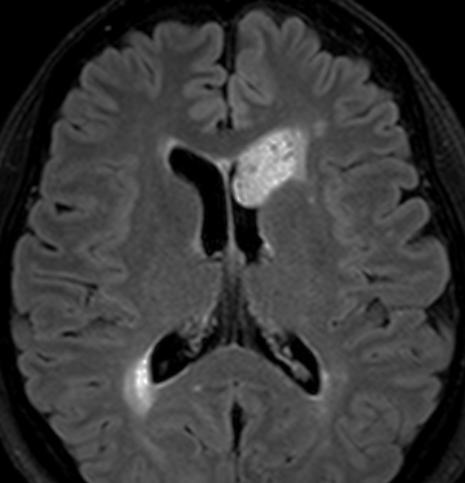

よくみつかる典型的な例です

中年男性に偶然発見された15mmくらいの上衣下腫です。側脳室前角の壁にピッタリくっつくようにキノコのように生えています。下の2枚はガドリニウム造影ですが増強されないのが特徴です。この点で中枢性神経細胞腫 central neurocytomaと区別できます。中枢性神経細胞腫はゆっくりですが大きくなる腫瘍です。でもこのような上衣下腫は大きくなるのはとてもまれです。小さいし水頭症にもならないので,なにも治療しないでほっておきます。間違っても開頭手術などしません。